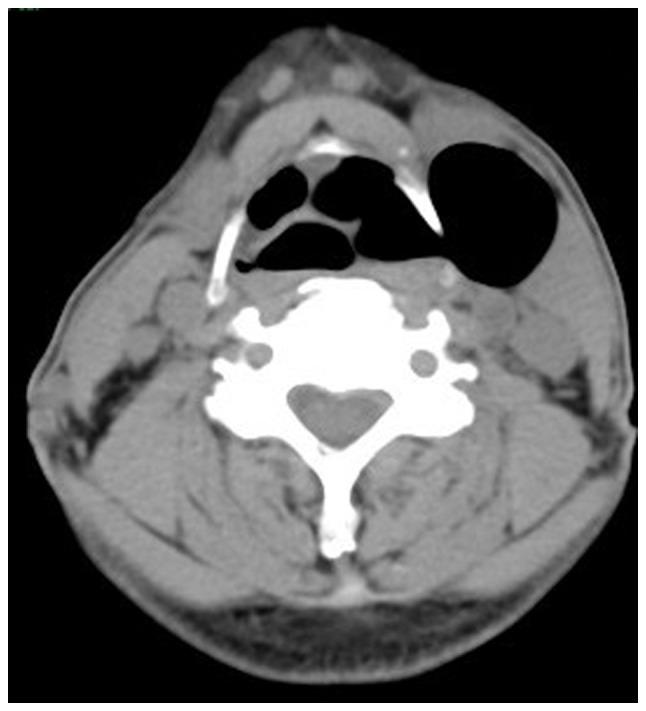

Laryngocele is a rare clinical condition characterized by an abnormal dilation of the laryngeal saccule. The present study focused on two separate cases of diagnosed patients. The first patient suffered from internal laryngocele and complained of hoarseness for almost 1 year. Plasma was used to treat the internal laryngocele and the outcomes were satisfying. The patient did not undergo any tracheostomy due to previous endoscopic surgery. The second patient included in the present study was diagnosed with mixed laryngocele and complained of swelling on the left side of the upper aspect of the neck with considerable pain for >1 month. The patient was prepped for excision by an external transcervical technique under general anesthesia. None of the two patients had any recurrence or other changes during follow-up. The purpose of reporting these two cases of laryngocele was to increase awareness of this condition. Surgery is still the first-line treatment for diagnosed cases, but with the advent of new microscopic techniques, the use of plasma in an inter-pharynx setting has become more common. The results observed after using plasma to treat one internal laryngocele may be relevant to better understanding the application of this method and confirm that it may be a new suitable approach to treat this condition.

喉膨出是一种罕见的临床病症,其特征为喉囊异常扩张。本研究聚焦于两例确诊患者。首例患者患有内喉膨出,主诉声音嘶哑近1年。采用等离子体治疗内喉膨出,效果令人满意。由于先前的内镜手术,该患者未进行任何气管切开术。本研究纳入的第二例患者被诊断为混合型喉膨出,主诉颈部上方左侧肿胀并伴有明显疼痛超过1个月。该患者在全身麻醉下通过外部经颈技术准备进行切除术。两名患者在随访期间均未出现任何复发或其他变化。报告这两例喉膨出病例的目的是提高对该病症的认识。手术仍然是确诊病例的一线治疗方法,但随着新的显微技术的出现,等离子体在咽内环境中的应用变得更加普遍。使用等离子体治疗一例内喉膨出后观察到的结果可能有助于更好地理解该方法的应用,并证实它可能是治疗这种病症的一种新的合适方法。